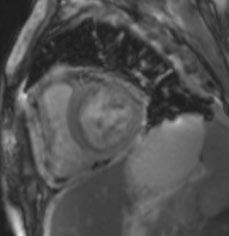

Receive our free newsletters and alerts Get the latest updates on all our upcoming journals and receive first-class insights into ground-breaking news and advancements in medicine across multiple therapeutic areas. www.emjreviews.com Join our mailing list

Turn static files into dynamic content formats.

Create a flipbook